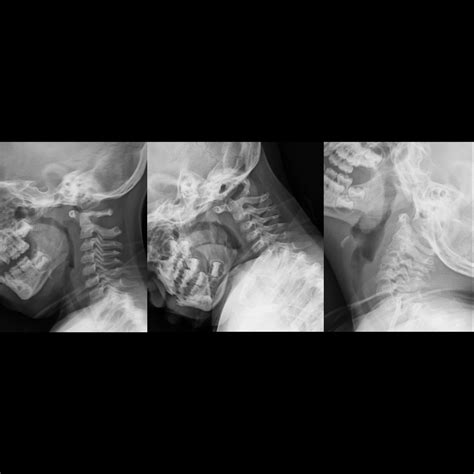

• X-rays: Often the first line of defense for bone fractures or lung issues.

X-ray Minimal Bone fractures, pneumonia, chest congestion